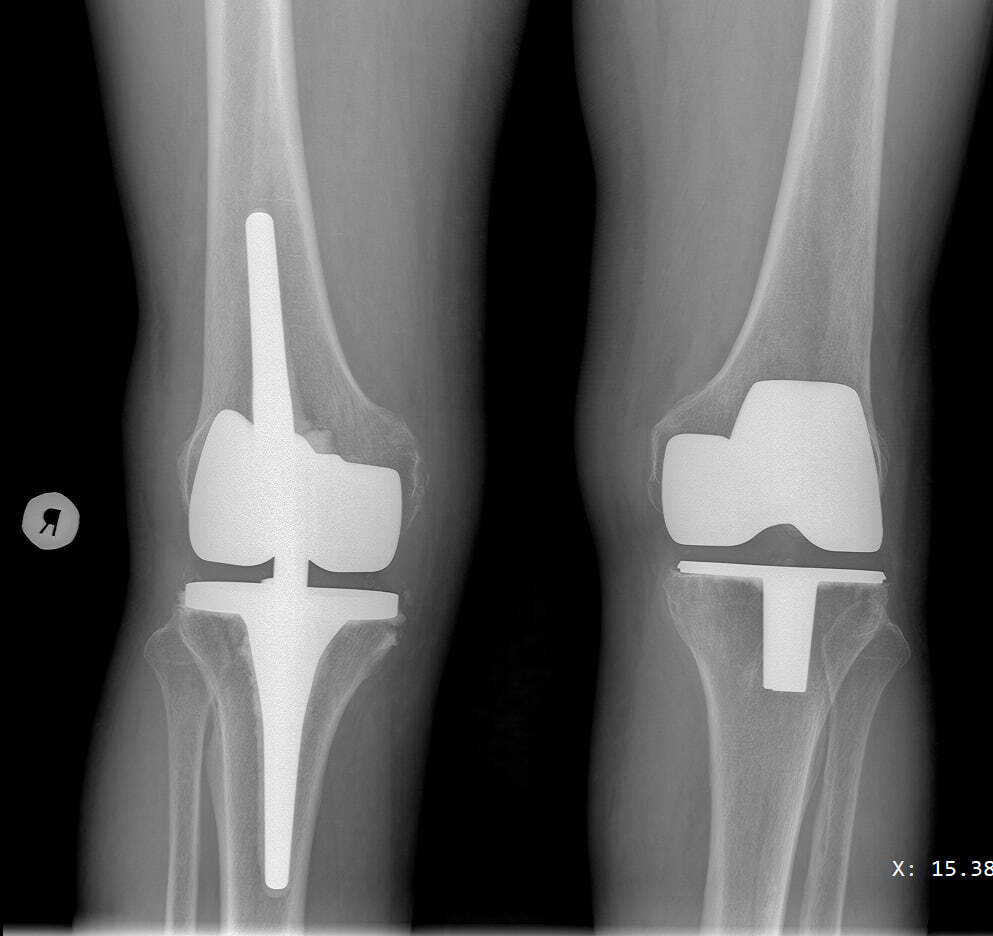

На снимке ниже эндопротезы тазобедренных суставов, которые ставились с разницей в три года: